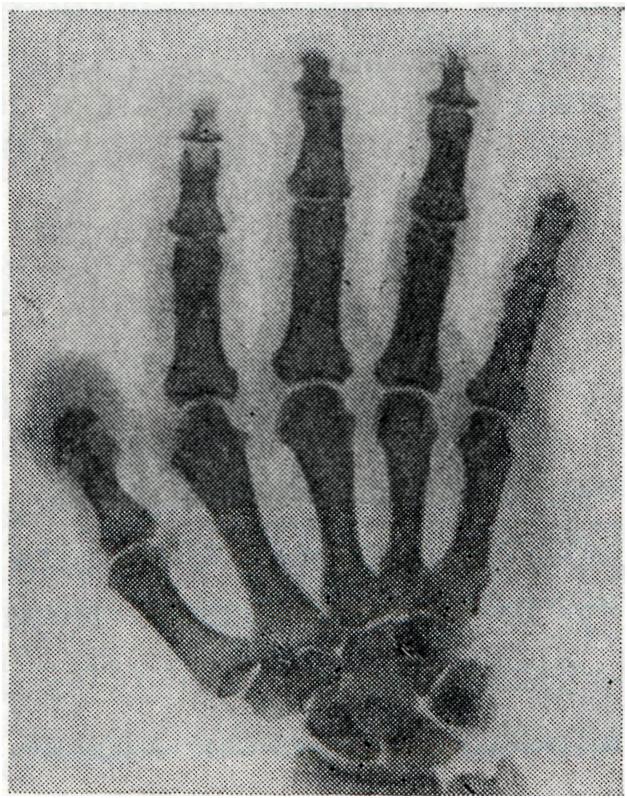

Артропатия нейрогеннаяАртропатия нейрогенная (arthropathia; греческое arthron сустав + pathos страдание, болезнь; синоним сустав Шарко) — вторичное дистрофическое заболевание суставов, развивающееся при поражении различных отделов центральной нервной ситемы; наиболее резко выражено при патологических очагах в области боковых рогов спинного мозга, его задних корешков и столбов, поражениях периферических нервов и гипоталамической области, обеспечивающих вазомоторно-трофическую иннервацию суставов. В происхождении артропатий нейрогенных основную роль играет потеря болевой чувствительности, расслабление связочного аппарата и мышц и обусловленная этим постоянная микротравматизация суставов, Артропатия нейрогенная наблюдается при сирингомиелии, спинной сухотке, диабетическом полиневрите. Кроме того, артропатии нейрогенные могут развиваться при нарушении мозгового кровообращения и некоторых других неврологических заболеваниях. Клиническая картина.При сирингомиелии артропатия встречается у 10—15% больных. Поражаются преимущественно локтевой и плечевой суставы, реже — суставы кисти (рис. 1), еще реже — другие. Это объясняется тем, что при сирингомиелии преимущественно поражается серое вещество спинного мозга на уровне шейных и верхних грудных сегментов»

У одних больных превалируют процессы гипертрофии, у других — атрофии костной, хрящевой и соединительной ткани. Суставные поверхности при этом деформируются. Появление внутрисуставного выпота, отечность мягких тканей и деформация внутрисуставных концов эпифизов приводят к увеличению размеров пораженного сустава. В мелких суставах кисти чаще наблюдаются явления деформирующего артроза, приводящего к искривлению пальцев. Несмотря на выраженность процесса, функция пораженного сустава нередко длительно сохраняется, а боли отсутствуют. Это объясняется тем, что при сирингомиелии снижается или полностью утрачивается болевая и температурная чувствительность. |

Рентгенодиагностика. Для артропатии типичны следующие основные рентгенологические признаки: рассасывание суставных концов костей (остеолиз), обезображивание их в связи с распадом костной ткани и бесформенными периостальными костными разрастаниями, остеосклероз, внутрисуставные и внесуставные патологические переломы и зоны перестройки в костях, беспорядочно расположенные параартикулярные окостенения и обызвествления, патологические вывихи и подвывихи. Своеобразной чертой артропатии является несоответствие между относительно мало нарушенной функцией сустава и грубыми морфологическими изменениями в нем. В связи с продолжающимся функционированием сустава суставные концы отшлифовываются, а отдельные костные отломки превращаются в суставные мыши.

Внесуставные переломы особенно часты при спинной сухотке (рис. 3), а лоозеровские зоны перестройки (смотри Лоозера зоны) — при сирингомиелии. Оба осложнения характеризуются образованием массивной периостальной костной мозоли.

При спинной сухотке (рис. 4) и сирингомиелии (рис. 5) возникают также внесуставные изменения в костях. Рентгенологически весьма типично рассасывание ногтевых фаланг пальцев кисти, начинающееся обычно с их свободного конца. Показательна картина заострения рассасывающихся концов костной культи. При табетической артропатии развиваются плоскостопие и genu recurvatum (дугообразное искривление ноги назад).